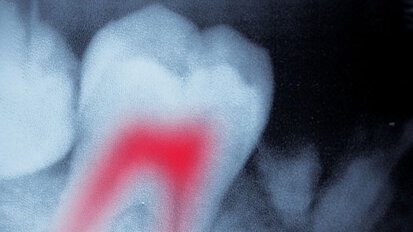

Study reveals that post-endo pain has different sources

CHICAGO, Ill. & MIAMI, Fla., USA: Tooth pain occurring after endodontic treatment might originate more often from another source than from the treated ...